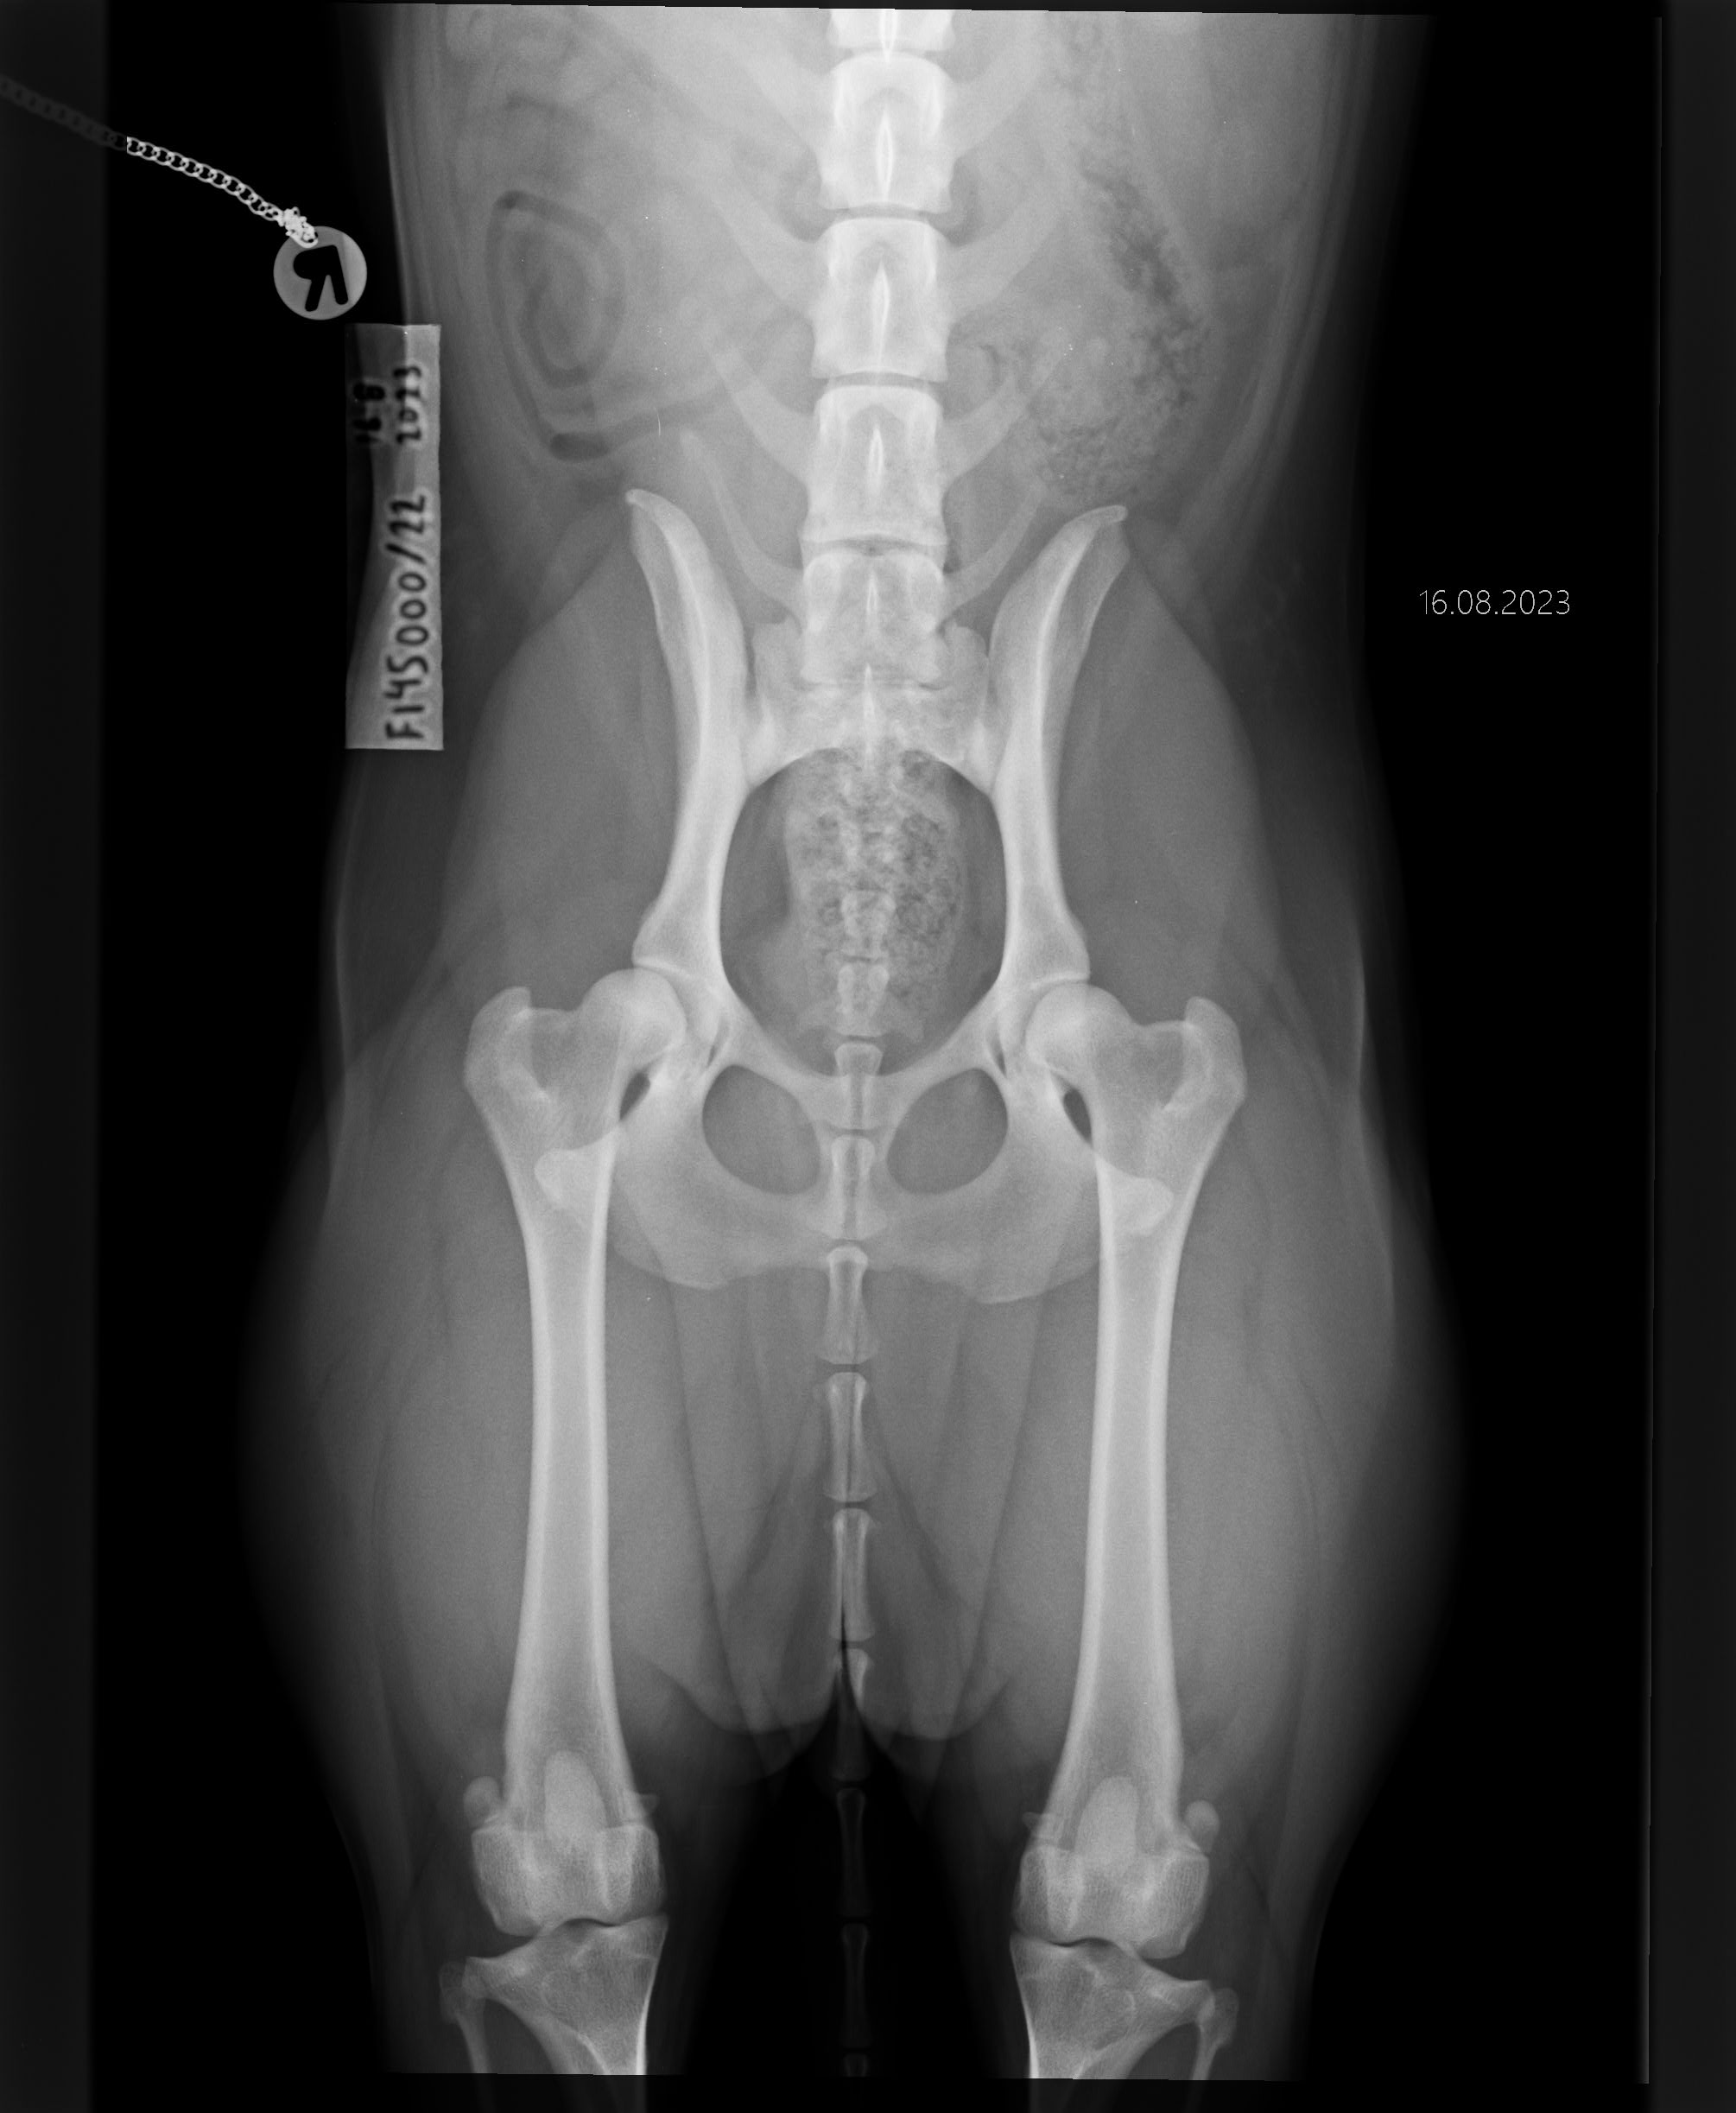

Lonkat

— B/B

«

»

Kyynärät

— 0/0